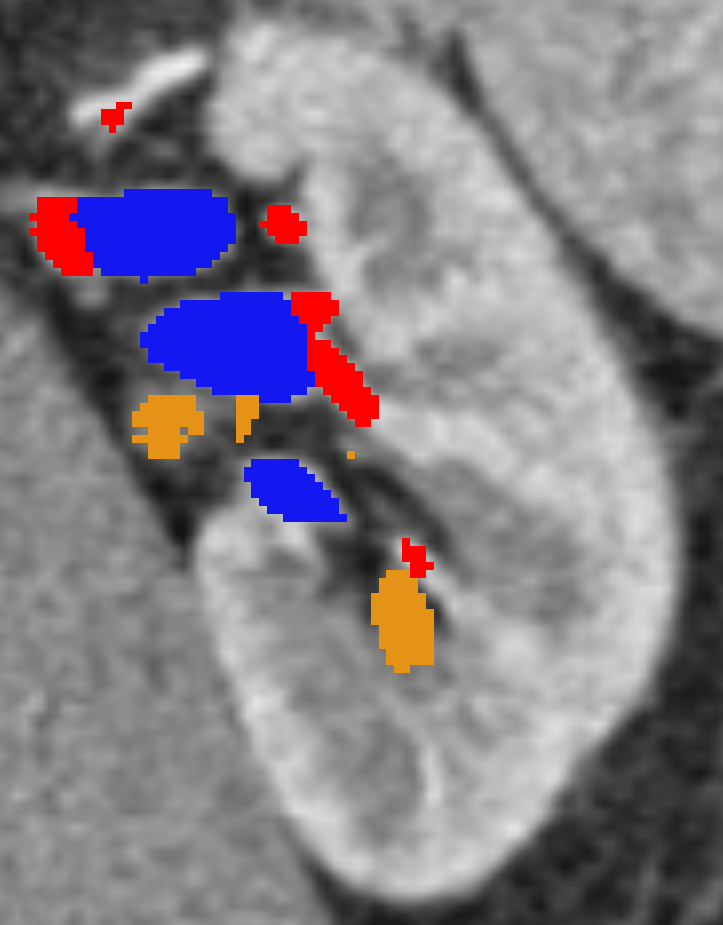

Due to background relative huge volume, it’s assigned tiny class weight. So the network produces a lot of false positives – it is cheap to mis-classify a background voxel. To tackle this undesired phenomena, we propose our second complementary fold – Random Sampling. Random Background voxels are sampled and assigned high weights. Such method is most effective in limiting false positives because high loss is incurred for these voxels if mis-classified. Figure 3 shows our sampling schema. Two bands are constructed around kidney vessels using morphological kernel, a binary circular dilation of radii two and four. Misclassifications within the first band ( voxels away from the vessel) are considered marginal errors. In a given patch, the sampled background voxels are equivalent to the foreground vessel volume, where and come from the red band and the volume beyond this band respectively. If a patch is foreground-free, voxels are randomly sampled.

Both artery and vein have tree-structure; they are thick near aorta and vena cava, while fine at terminals near renal artery and renal vein. These fine vessels are most difficult to annotate, i.e. most valuable to acquire. Dice-coefficient is biased against fine details in such tree-structure. To overcome such limitation, we evaluate the two regions depicted in figure 3. The first region is based on the ground truth region of interest. This evaluates the whole tree-structure including the thick branches– aorta and vena cava. The second region is the kidney bounding box. It targets fine vessels in direct contact with the kidney.